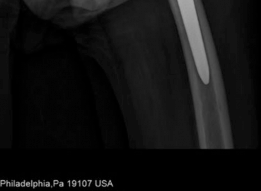

Previous surgical procedures : Right total hip arthroplasty 2008, left total hip arthroplasty 2011, inferior vena cava filter (Fig. 19.22).

Fig. 19.22 Most recent routine follow-up PA pelvis, prior to emergency department presentation. Evidence of significant femoral peritrochanteric and pelvic periacetabular osteolysis